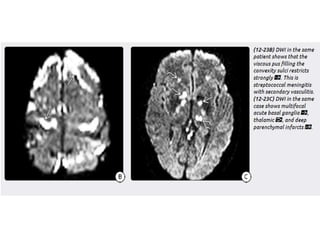

Complications

• The complications of meningitis can be remembered using the

mnemonic HACTIVE :

• H: hydrocephalus

• A: abscess

• C: cerebritis / cranial nerve lesion

• T: thrombosis

• I: infarct

• V: ventriculitis / vasculopathy

• E: extra-axial collection: empyema and hygroma